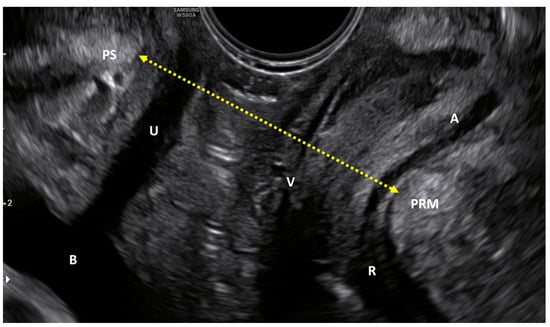

2.3. Quantitative Evaluation with Ultrasounds

3.1. Quantitative Evaluation: Ultrasound Measurements